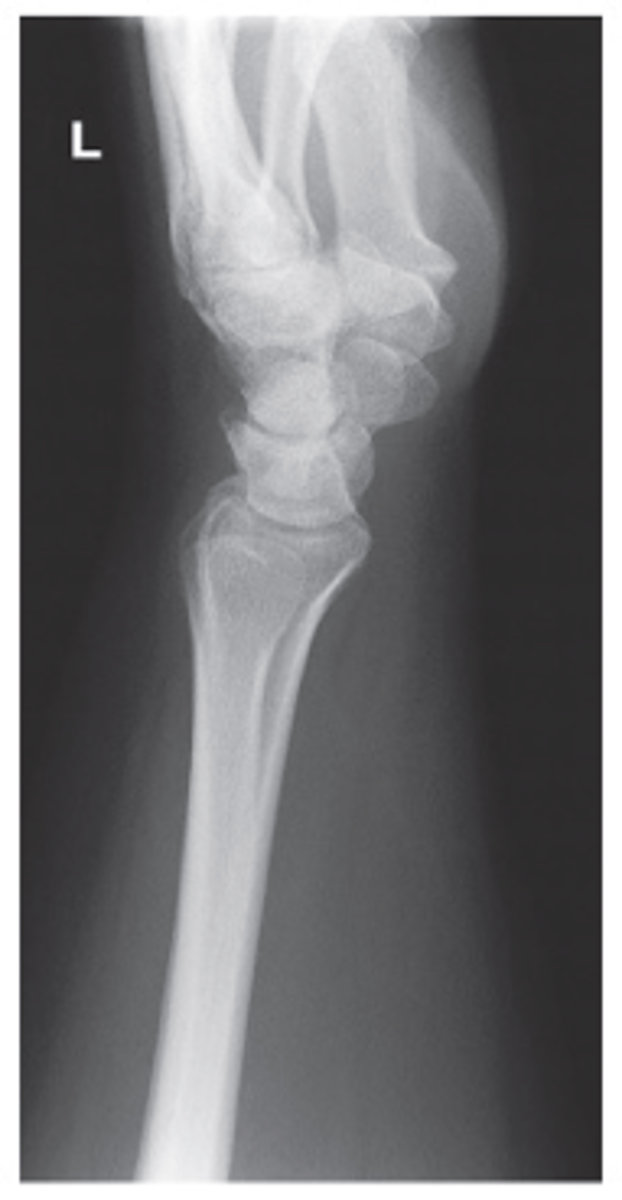

PA Oblique Wrist

Lateral wrist